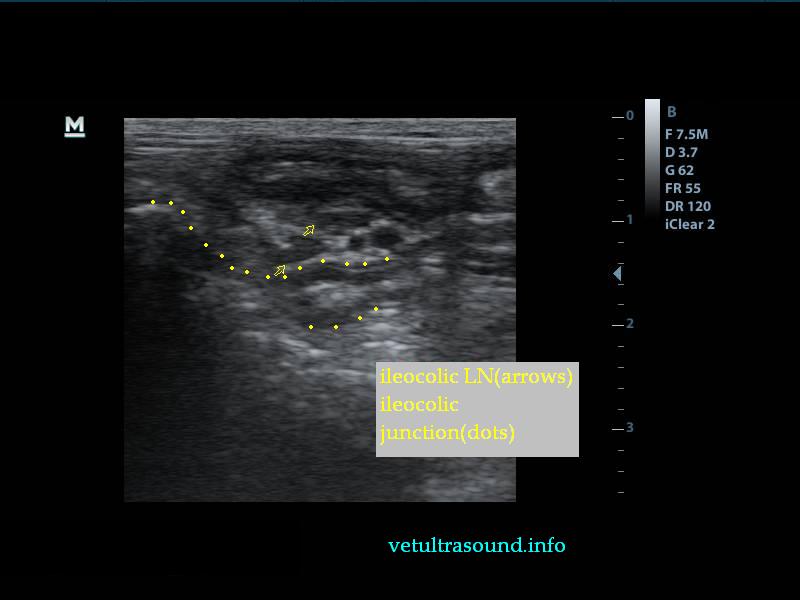

Στον υπέρηχο βρέθηκε ανομοιογένεια του ηπατικού παρεγχύματος, πολυάριθμοι κυστικοί σχηματισμοί οι οποίοι καταλάμβαναν κυρίως τον δεξιό πλάγιο λοβό του οργάνου(pic1&2). Η ροή του αίματος στη πυλαία φλέβα με τη βοήθεια του Pulse Wave Doppler βρέθηκε φυσιολογική(pic3), ενώ σε κλάδο της δεξιάς ηπατικής αρτηρίας ο δείκτης αγγειακής αντίστασης βρέθηκε μειωμένος(normal RI≈ 0.55)(pic4). Στοιχείο που μας δείχνει πως είτε η αγγείωση στη συγκεκριμένη περιοχή είναι νεόπλαστη, είτε λόγω χρόνιας νόσου ο διάμεσος ιστός που περιβάλλει τα αγγεία έχει χάσει την σκληρότητά του. Μικρή ποσότητα ασκιτικού υγρού βρέθηκε ανάμεσα στις εντερικές έλικες. Χωρίς παθολογικά διογκωμένους λεμφαδένες εκτιμήθηκε η κοιλιακή κοιλότητα(pic5). Οι υπόλοιπες δομές ελέγχθηκαν χωρίς παθολογικά ευρήματα.